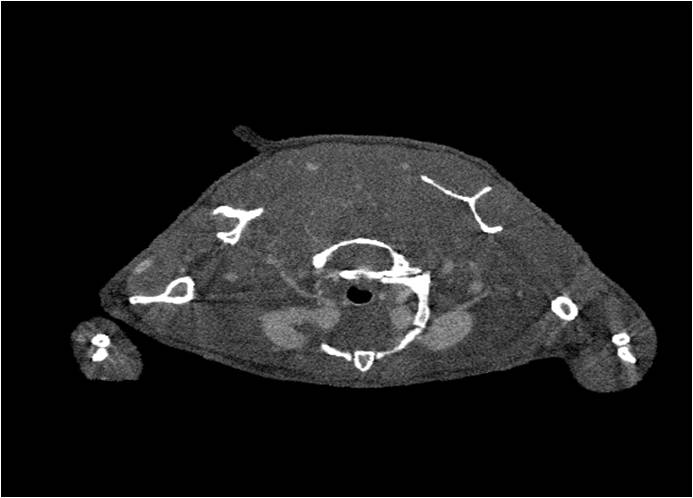

胸部和心血管的層析成像                                       胸部和心血管的3D圖像

心血管.jpg     心血管1.jpg